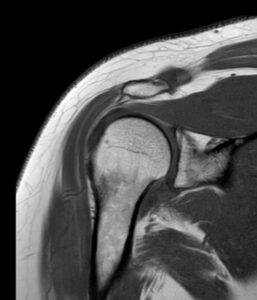

A ressonância magnética ao ombro é um exame de imagem não invasivo, sem radiação, que permite avaliar com detalhe as estruturas internas do ombro, incluindo músculos, ossos, ligamentos, tendões e cartilagens. É indicada para o diagnóstico de lesões como tendinites, roturas do manguito rotador, bursites e instabilidade articular.

A ressonância magnética (RM) ao ombro recorre a campos magnéticos e ondas de radiofrequência para produzir imagens em alta resolução dos tecidos moles e estruturas ósseas da articulação do ombro. É particularmente útil para identificar lesões não visíveis em radiografias ou tomografia.

A ressonância magnética ao ombro permite identificar com precisão:

- Tendinites e tendinopatias do manguito rotador (supraespinhal, infraespinhal, subescapular e pequeno redondo);

- Roturas parciais ou completas dos tendões do manguito rotador;

- Bursites subacromiais ou subdeltoideias;

- Lesões do tendão bicipital e instabilidade da cabeça do úmero;

- Alterações da cartilagem glenoumeral e do lábio glenoidal;

- Irregularidades ósseas, pequenas fraturas ou edema ósseo;

- Síndrome do impacto subacromial e outras alterações mecânicas;